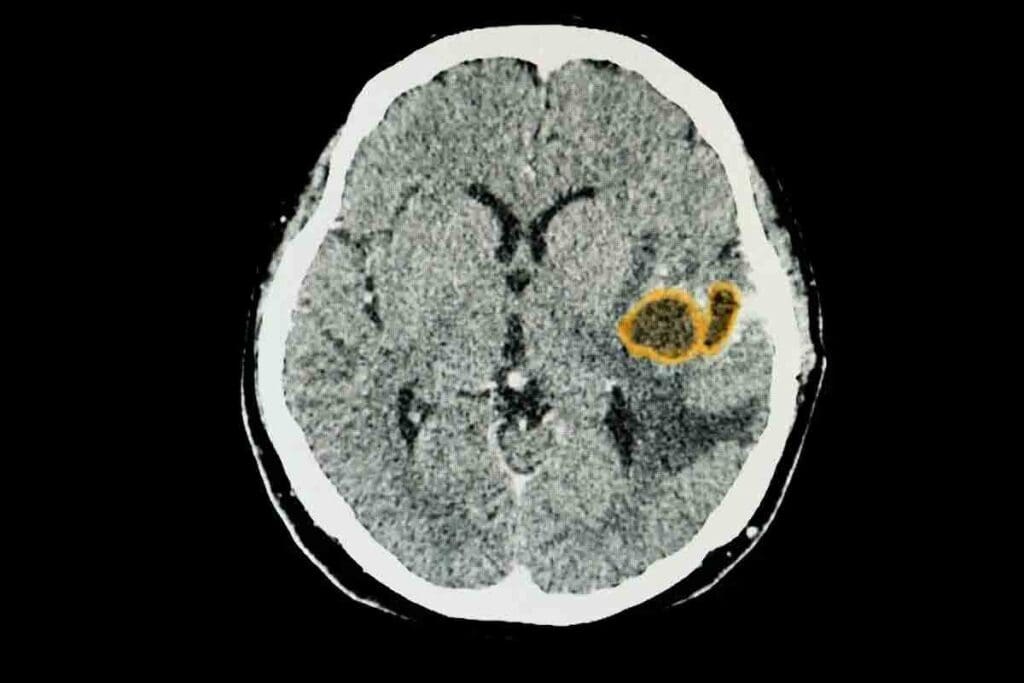

Brainstem Gliomas: Comprising 10% of Childhood Brain Tumors

Brainstem gliomas are rare and complex tumors that mostly affect kids. They start in the brainstem’s glial cells. This area is key for controlling automatic body functions like breathing and heart rate.

Anatomical Location and Significance

The brainstem is made up of the midbrain, pons, and medulla oblongata. It’s vital for sending signals between the brain and the body. Tumors here can greatly affect a child’s life and treatment is hard because of its importance.

The location of brainstem gliomas is key. It affects symptoms and treatment options. Tumors can press on or get into nearby nerves, causing many problems.